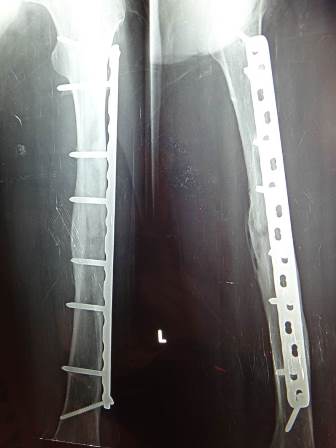

5-year follow-up X-ray